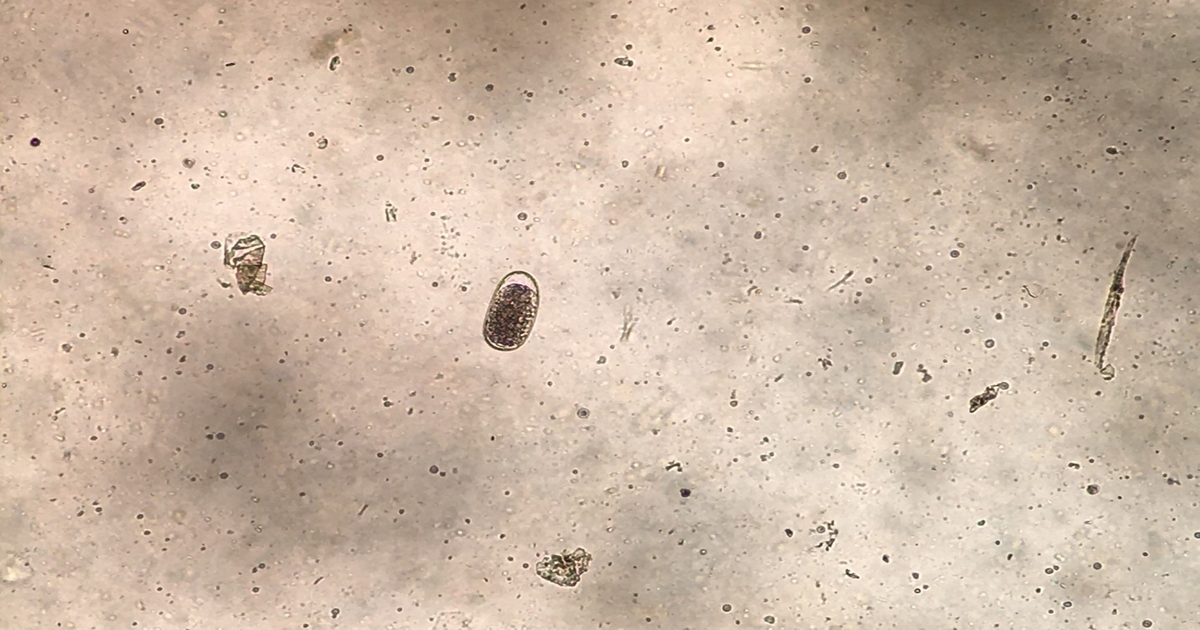

Cell study provides bovine TB vaccine insights

Inoculation stimulates activity in key immune cells in cattle, offering insights into improved vaccine design.